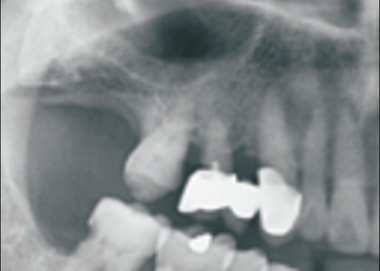

Обзорный снимок до лечения. Удлинение и наклон 15 и 16 зубов вследствии кариеса. Показана экстракция.